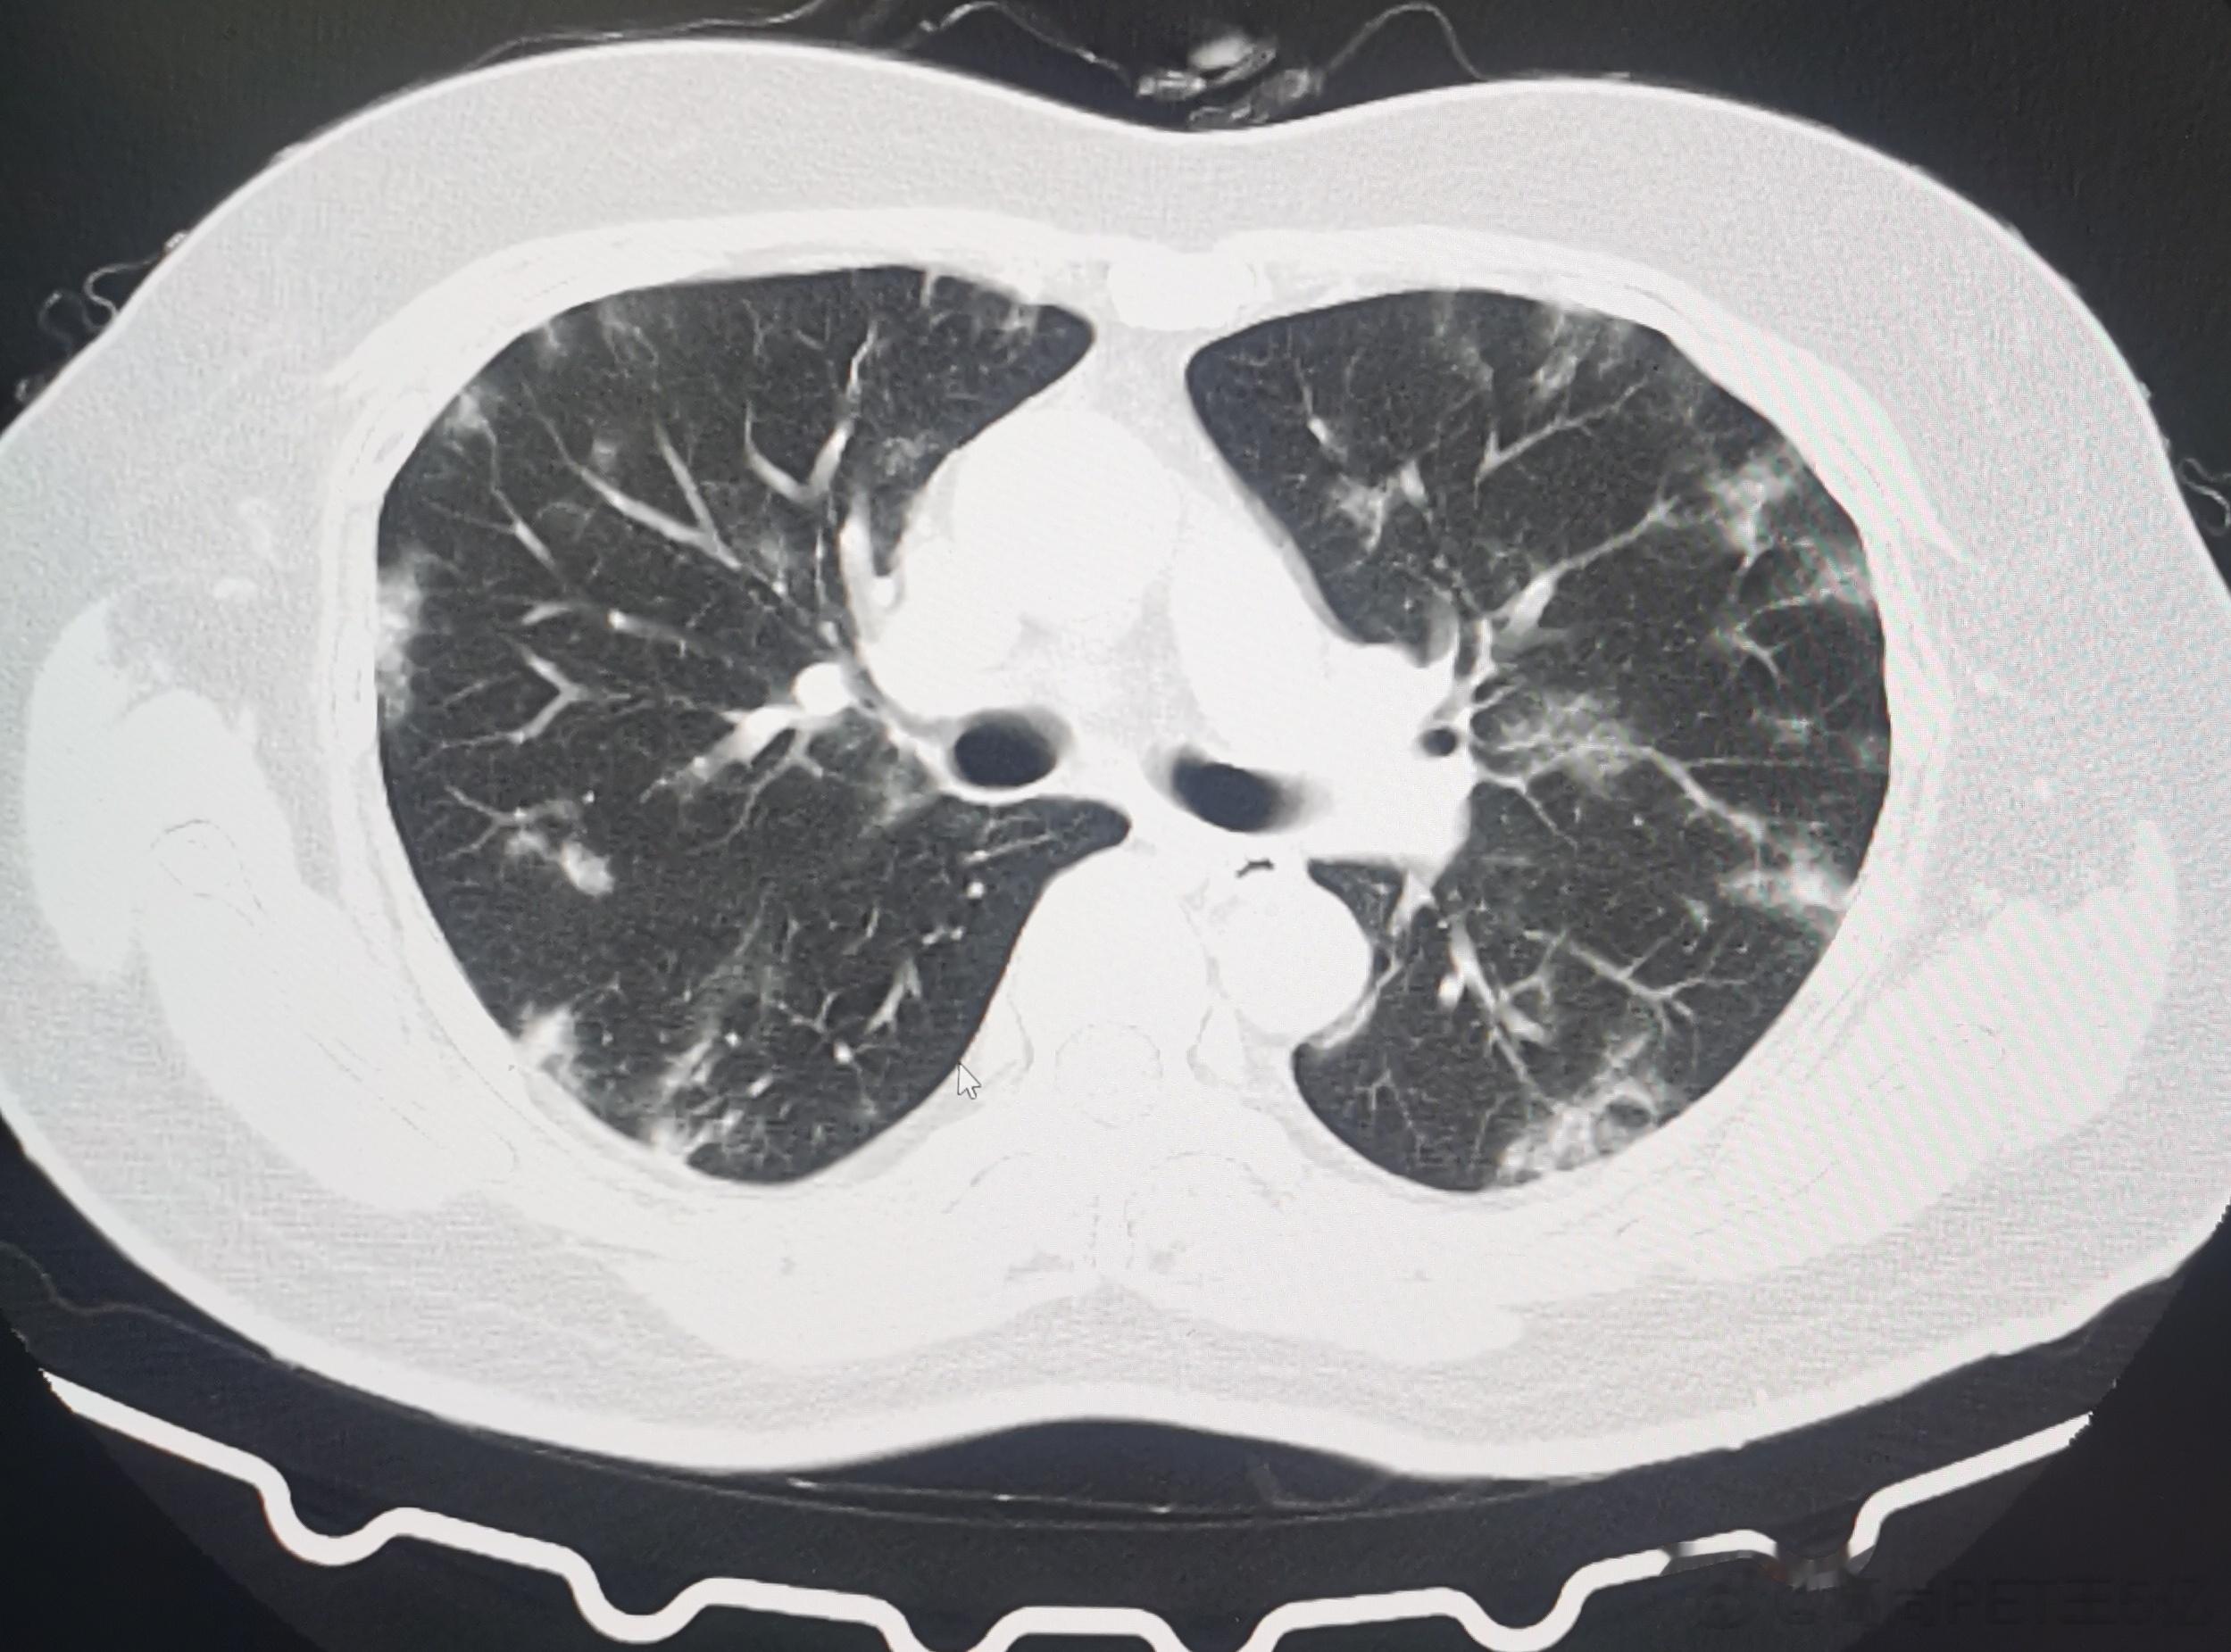

今日我们高尚影像中心新冠肺炎筛查病人是108例,其中28例有轻度新冠肺炎影像表现,检出率接近26%,最最小14岁(下面第一排CT图像),最大年龄是87岁(下面第二排CT图像),大部分人的年龄超过60例。由此可以看出,新冠病毒肺炎可能会累及各个年龄段,但主要还是60岁以上老年人群。如果新冠感染超过2周咳嗽症状还不减轻者,最好做一个胸部CT判断有无新冠病毒肺炎,这对于决策治疗方案及预测治疗效果都很关键。#老年人感染新冠后小心肺炎##感染新冠都要做CT吗#

今日我们高尚影像中心新冠肺炎筛查病人是108例,其中28例有轻度新冠肺炎影像表现,检出率接近26%,最最小14岁(下面第一排CT图像),最大年龄是87岁(下面第二排CT图像),大部分人的年龄超过60例。由此可以看出,新冠病毒肺炎可能会累及各个年龄段,但主要还是60岁以上老年人群。如果新冠感染超过2周咳嗽症状还不减轻者,最好做一个胸部CT判断有无新冠病毒肺炎,这对于决策治疗方案及预测治疗效果都很关键。#老年人感染新冠后小心肺炎##感染新冠都要做CT吗#